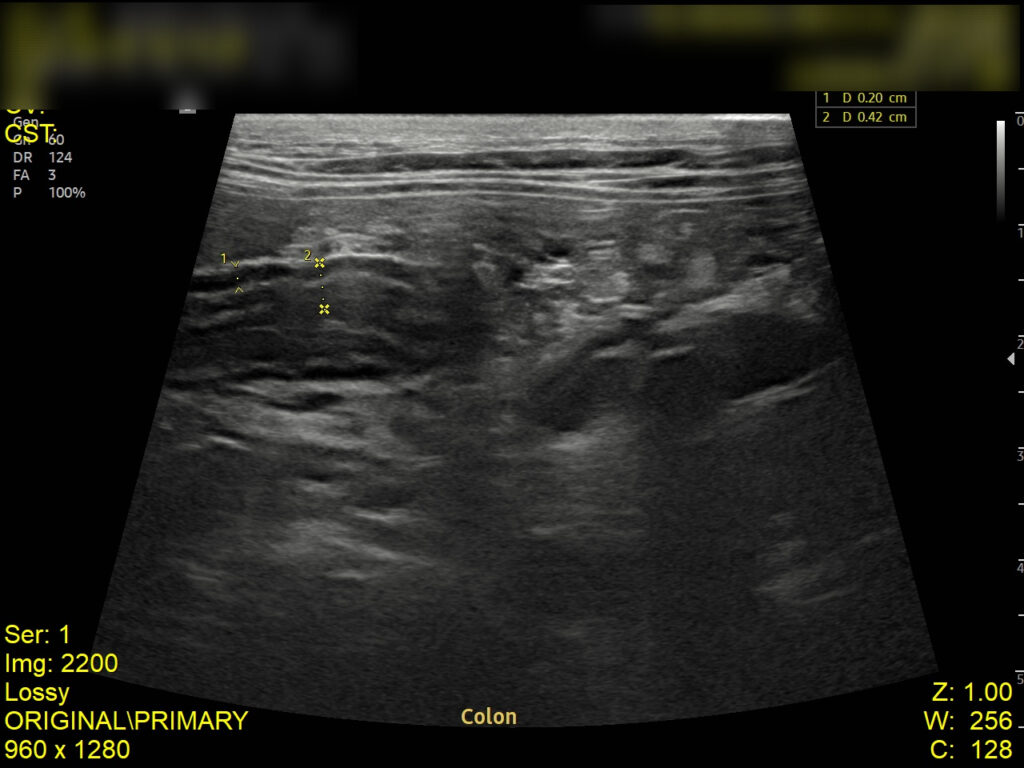

복부 초음파 검사 결과

초음파 검사 결과, 복강 내 림프절이 비대된 모습이 확인되었고, 장벽 두께가 정상보다 두꺼워진 것을 확인되었습니다. 이는 장 내 염증 반응이나 감염성 원인에 의해 장벽이 자극을 받고 있음을 의미합니다.